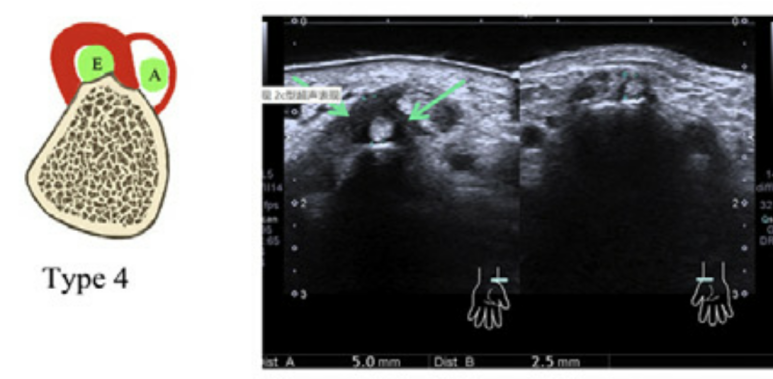

그 중 특히 주목해야 할 타입이

바로 'Type 4' 같은 환자들입니다.

엄지를 들어 올리는 '단무지신근(EPB)' 힘줄과

그 주변 터널에만 염증이 있고,

바로 옆에 있는 '장무지외전근(APL)' 힘줄은

아주 건강한 상태입니다.

생각해보세요.

두 개의 힘줄 중 범인은 오직 하나인데,

만약 이 사실을 모르고

터널 전체에 주사를 놓는다면 어떨까요?

불필요한 정상 부위까지 자극하게 되는 셈이고,당연히 치료 효율도 떨어질 수밖에 없습니다.

이런 경우에는

'진짜 범인'인 EPB 힘줄만

단독으로 치료하는 것이 효과적입니다.